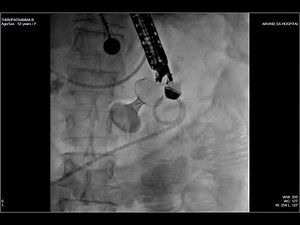

- Gastrojejunostomy

Surgery - Billroth

2 - Jejunostomy